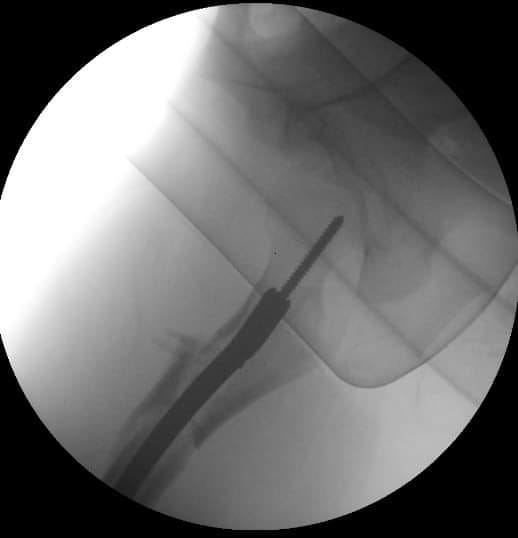

Вот, что получилось.

Александр, Почему в шейку и головку? почему не в направлении малого вертела привели блокирующий винт? Это оригинальный винт или...?

почему бы и не в шейку... Если есть такая дырочка и в гвозде, и в направителе. В physis винт не проникает.

Винт, конечно, из набора.

Винт, который проходит перпендикулярно зоне роста проблем не вызывает. Таким образом делается эпифизиодез при юношеских эпифизиолизах и в перспективе на рост кости не влияет. Поэтому производитель не зря придумал шеечный винт в данном стержне

Эпифизиодеза у нас в планах не было, поэтому винтик не до суставной поверхности. В общем, если железка не проходит через зону роста, то и беспокоиться особо не о чем, правильно?

На прямой проэкции видно, что винт проходит физиодезный мостик. Даже если был бы длиннее, тоже не критично.

Вопрос- насколько «заглушка» прижимает шеечный винт?

Извините

С торца ничего не введено- или кажется?

И - винт в ШБК - сам по себе?

нет, ничего не вводил. Предусмотрена там возможность ввести end cap - не делаю этого обычно.

Винт просто введён в отверстие в гвозде.

Be careful and watch

Данный винт априори нестабилен.

К сожалению, имею опыт нарушения growth plate именно при таком (граничном расположении ) винта